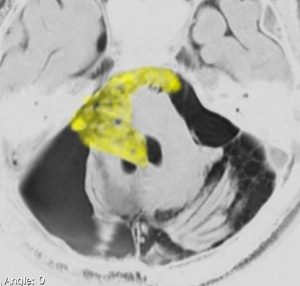

30歳くらいの時に初回の開頭手術で部分摘出を受けて,現在70代の患者さんの画像です。黄色は今も残っている腫瘍です。2度目の開頭手術,3度目の開頭手術では癒着で脳幹部や脳神経からの剥離が全くできませんでした。現在でも脳幹部に入り込むように腫瘍がゆっくり大きくなっていて,体幹失調のために車椅子生活です。顔面神経麻痺,嚥下障害,構語障害,眼球運動障害などもあります。髄液吸収障害による水頭症を併発してシャント手術も受けています。

この患者さんの40年の経過はいろいろなことを教えてくれます。似たような患者さんをたくさん見てくると,初回手術で取りきれなかった類表皮のう胞を,2度目の開頭手術で完全摘出することはとても難しいという経験を積みます。

数十年後のことを考えるのであれば,初回手術で完全摘出するべきです